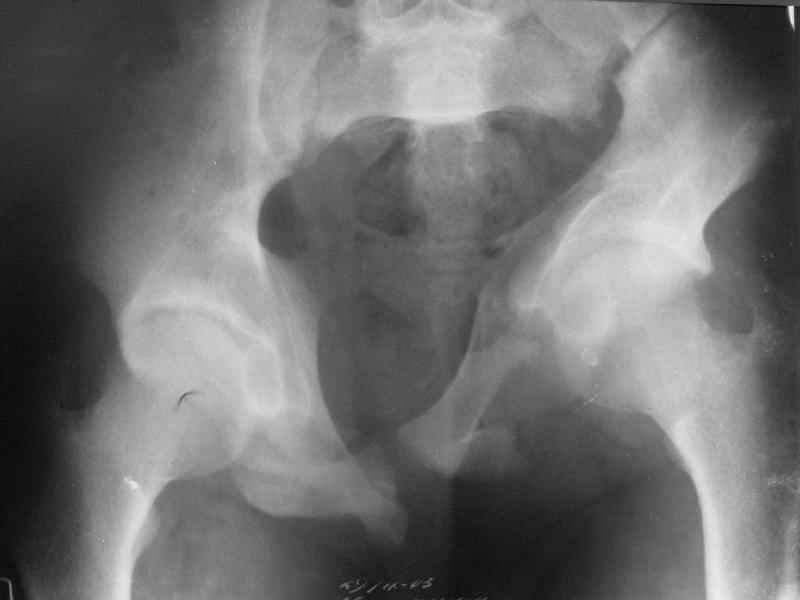

Коллеги, помогите определиться с тактикой лечения пациента. Ув. коллеги, к нам поступил молодой человек 17 лет. Травма в июле 2005- ДТП, т.е. 3 мес назад. Лечился консервативно в "гамаке" 1,5 мес., затем ходьба с костылями без опоры на левую нижнюю конечность, начал на нее опираться 1 нед назад. В настоящее время имеется укорочение порядка 4-5 см, выраженная хромота, передвигается с одним костылем. Кроме того беспокоят боли в пояснично-крестцовой области при ходьбе, неудобство при сидении, невозможность лежать на спине "на жестком", а также на левом боку (субъект худощавый, боль в области крыла) хромота, длительное пребывание на ногах невозможно. На функциональных снимках большой подвижности нет (не привожу из-за плохого качества). Учитывя наличие участков сращений, помогите опредилиться с тактикой. Наш план пока такой: 1. выполнить остеотомии в участках сращений 2.постепенно аппаратом низвести смещенную половину таза. 3.выполнить внутренний остеосинтез передних и задних отделов. Будем признательны за ваш взгляд на тактику леченияэтого больного, а так же на такие проблемы как: места остеотомий, возможные варианты компоновки аппарата, выбор имплантатов для последующего вмешательства.

Уважаемый коллега. Не знаю, прооперировали-ли вы больного или нет, но глядя на Р-граммы захотелось поделится сосбражениями. Укорочение конечности на 4-5 см конечно-же нужно устранить. Вы хотите выполинть остетомию мест сращения, любопытно каким образом? Если пользоваться широкими доступами, то возможно выпонить репозицию открыто и фиксировать погружнными конструкциями как Вы и планируете после репозиции в аппарате. Тем самым устранить укорочение конечности, может быть конечно не оплностью но на 2-3 см то точно. Закрыто же выполнить остеотомию сращений наверное возможно сзади, спереди я бы не рискнул, а лонные кости рубить надо. Что касается лечения аппаратом, то я ученик "вашей школы" что вашим аппаратом можно устранить смещения полностью. Но стоит ли подвергать пациента длительному дискомфорту и повышать риск воспалительных осложнений? Учитывая Ваш опыт лечения таких повреждений таза я бы остановился на одномоментной открытой репозиции и остеосинтезе. С уважением Гринь Алексей.